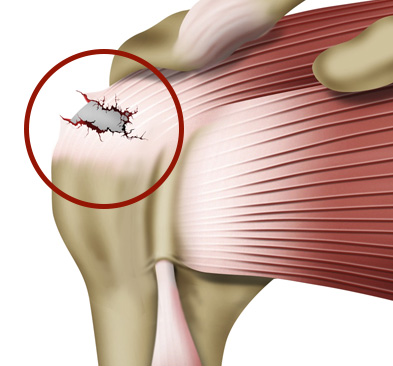

어깨 통증을 동반하며

근력이 떨어지는 경우

MRI상 회전근개 파열이

진행되는 경우

아무리 힘을 줘도

팔이 올라가지 않는 경우

관절염의 말기, 보존적 치료에

반응하지 않는 경우

주사,비수술치료에도

통증이 지속되는 경우

10번의 비수술보다 단 1번의 수술로 해결됩니다!

완전 파열시